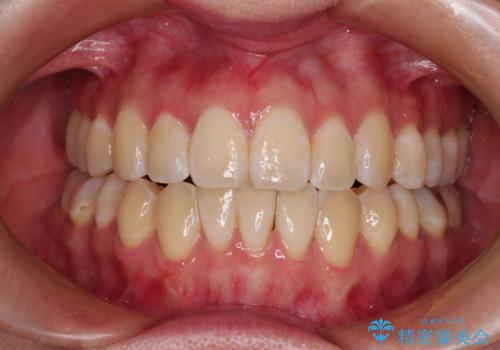

外に飛び出して磨きにくい奥歯と上下前歯の隙間 インビザラインによる矯正治療

下顎前歯が1本欠損しており、上下アーチはアンバランスとなりますが、インビザラインを用いて上下の隙間を改善しながら歯列を整えることとしました。

外側を向いている奥歯は、内側にアンカースクリューを埋入して牽引の固定ゲント氏、部分的にワイヤー装置を用いることで歯列に納めることとしました。

下顎前歯の1本欠損により左右の咬合が不安定となり、治療経過で噛みにくい状態が続きましたが、最終的には違和感なく噛めるようになりました。